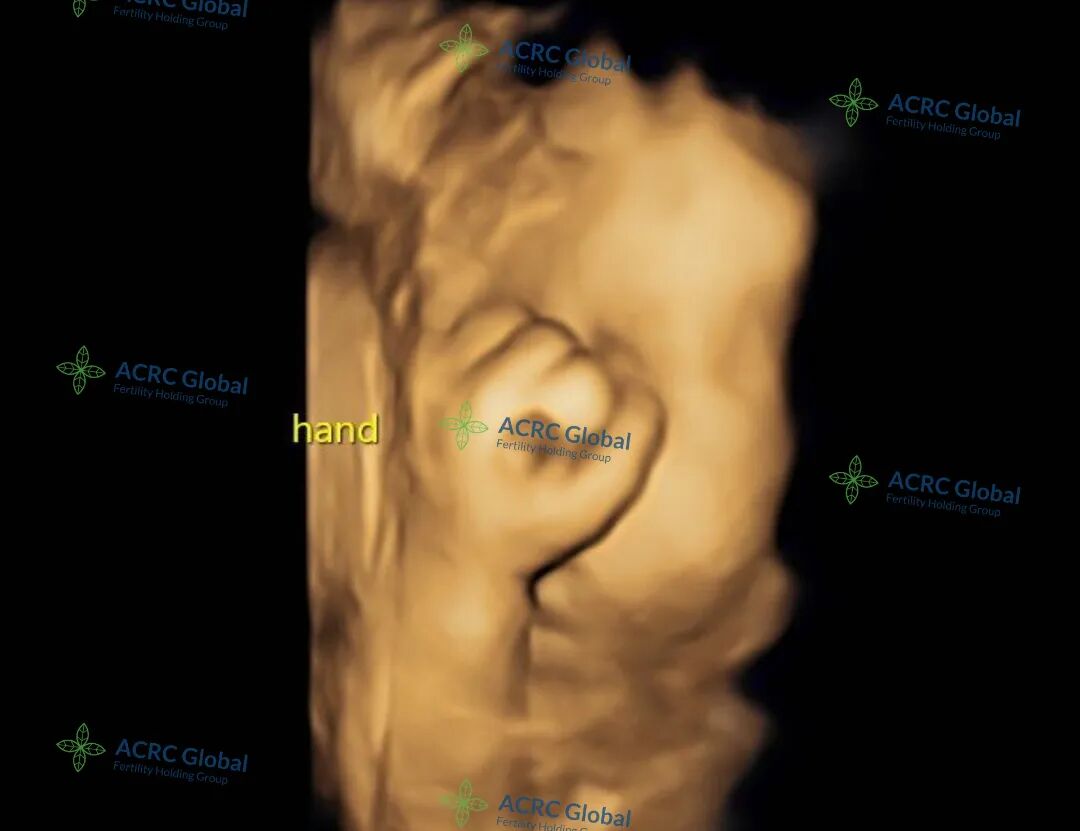

爱妈E的三维B超显示,宝宝已经37周了,体重达到六磅多,已经足月,小脸蛋看上去圆润饱满、十分可爱。虽然小手轻轻挡住了脸蛋,但从侧脸的轮廓中依然可以看出她那精致的小公主模样。医生预估,宝宝在出生时将会有七磅左右。准父母已经满怀期待地准备迎接宝宝的到来,期盼着和她的第一次见面呢!